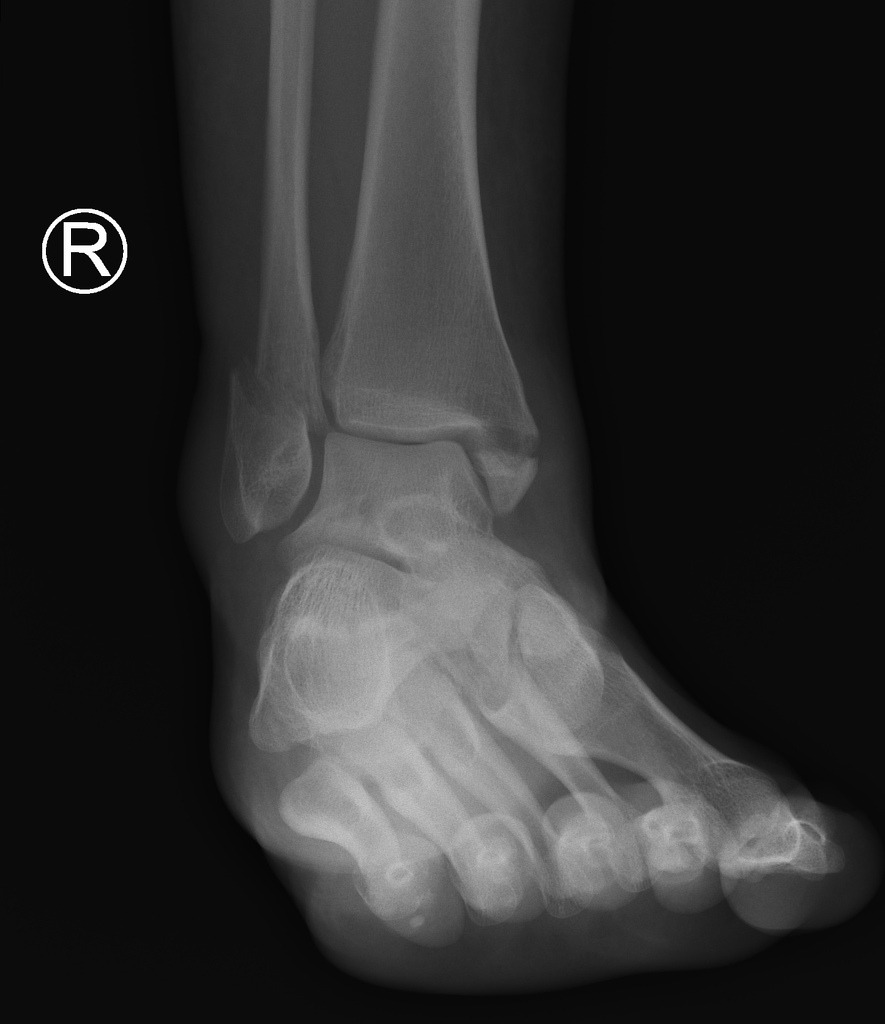

Ankle X Rays.

(Photo : dontforgetthebubbles.com)